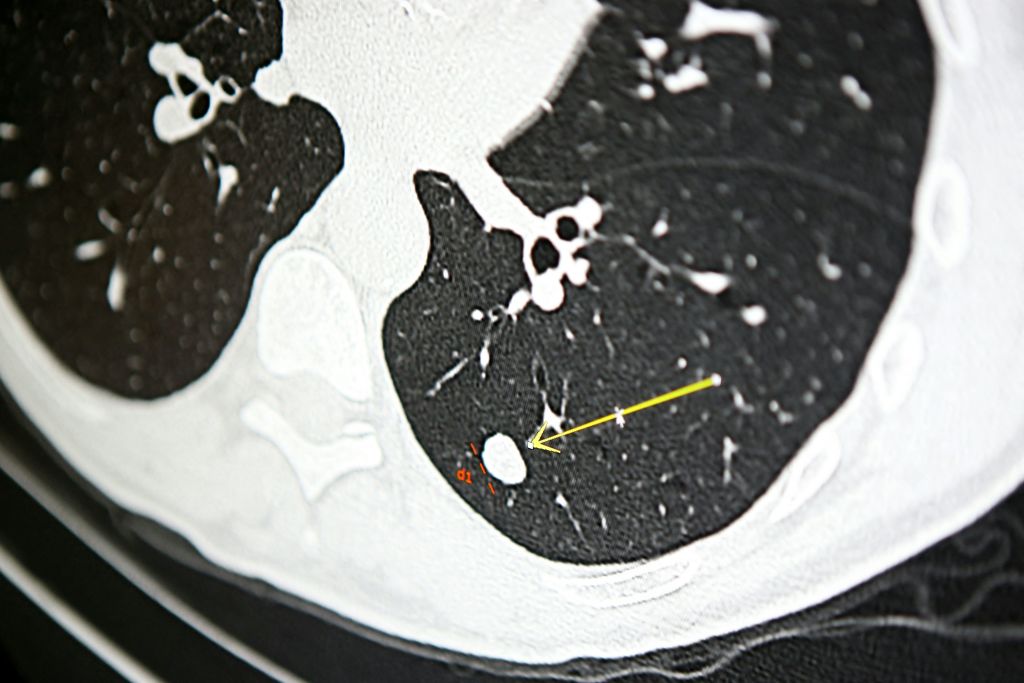

がん予防のための食事は、いつの時代も関心の高いテーマだ。最近の研究によりサルナシ果実が肺がん予防に役立つことが明らかになった。

岡山大学大学院医歯薬学総合研究科の有元佐賀惠准教授を中心とする研究チームは、サルナシ果汁をマウスに水代わりに飲ませた結果、肺発癌物質による肺悪性腫瘍の発症数が減少したと明らかにした。

学会誌「Genes and Environment」に掲載された研究論文によると、サルナシ果実に含まれるイソクエルシトリン(isoQ)は、がん増殖に対するPI3K/AKTシグナル伝達経路を遮断して、肺がん細胞の増殖を抑制する作用があることが示されたという。

研究グループは、「日本で一番死亡数の多い肺がんの予防法解明への一歩となることが期待される」と述べた。